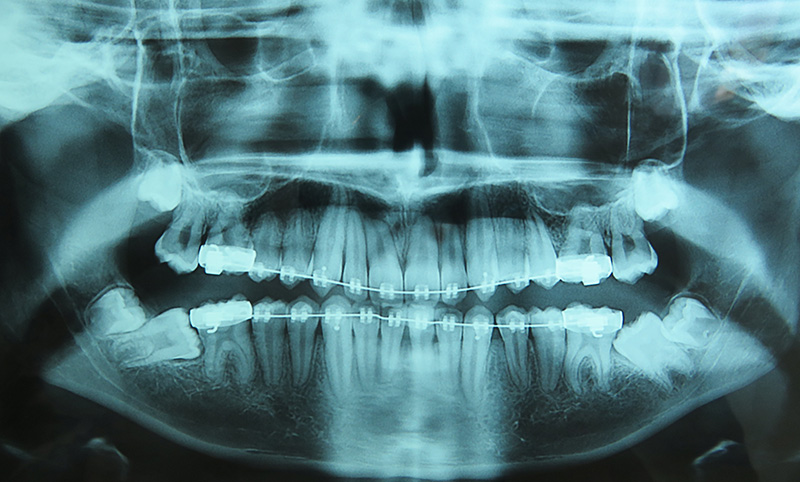

La vache copié collé de ma radio

Me suis tapé une carie, première de ma vie à cause de ces salopes